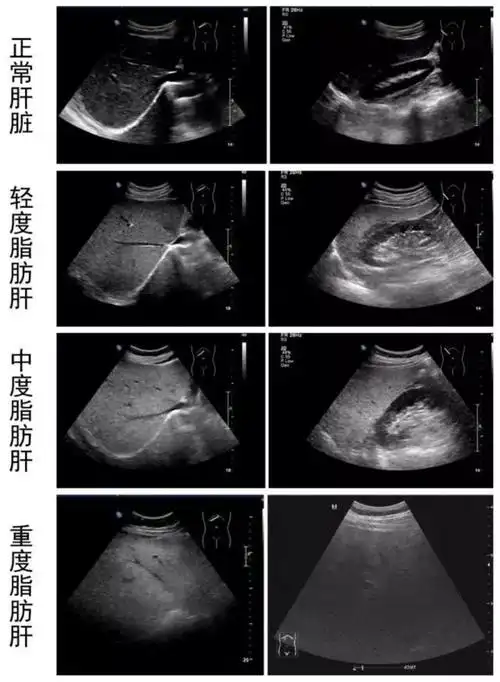

超声医生眼中的"脂肪肝"_诊断